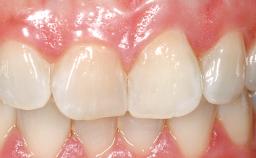

Immediate Flapless Placement of an Implant in a Maxillary Right Lateral Incisor Site

This 43-year-old male patient, a non-smoker, came to our practice because of a fracture of tooth 12 caused by a bicycle accident. Due to the combined para- and infrabony crown and root fracture, tooth extraction, and subsequent implant placement were suggested to the patient as the therapy of choice. The patient had high esthetic expectations with regard to the treatment outcome and asked for an immediate fixed provisional restoration. His individual esthetic risk profile summed up to a medium esthetic risk.